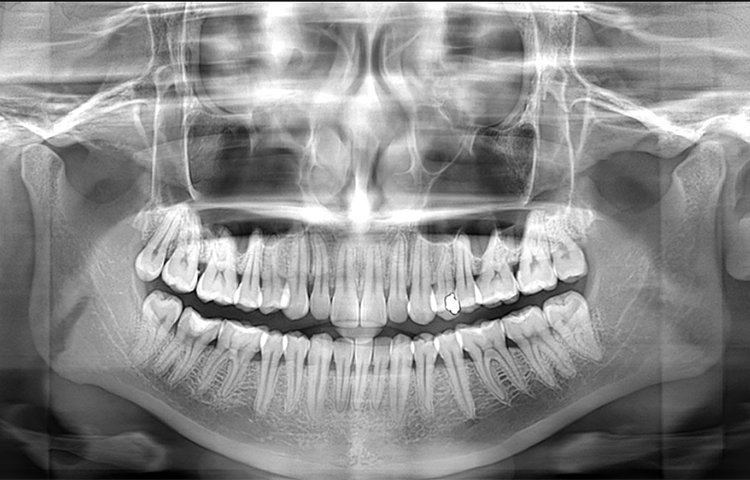

La máquina panorámica dental de Meyer proporciona a los dentistas imágenes panorámicas de alta calidad y vistas laterales, que pueden usarse para diagnosticar la dentición completa, la mandíbula y la articulación temporomandibular. También es adecuada para el diagnóstico de fracturas maxilofaciales y para el diseño de planes de ortodoncia.

Galería de imágenes